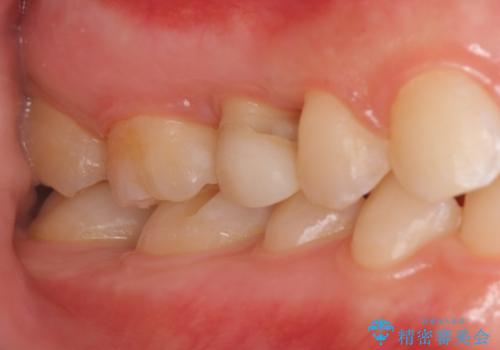

- 他院で治療途中、歯を被せたら頻繁に外れてしまうとのことでした。

診察すると、歯の高さがなく物理的に外れやすい状態となっていました。

歯周外科治療で歯の高さを出し、外れにくくしました。

高さがなく外れやすいことに関しては、高さを出す以外にないのですが、向かい合わせの歯があるため、被せ物の高さを高くするわけにいきません。